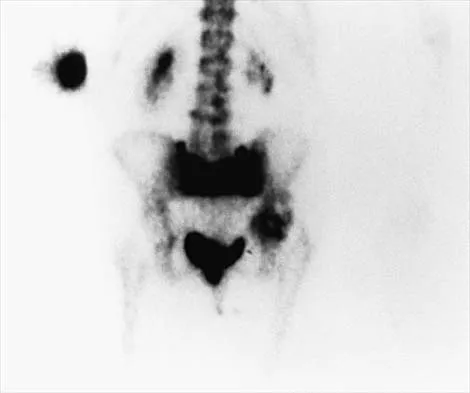

An 82-year-old woman reports right buttock pain after a car trip. Laboratory studies show an erythrocyte sedimentation rate of 30 mm/h and WBC of 4,600/mm3. Figure 34a shows a plain AP radiograph of the pelvis, and Figure 34b shows a delayed technetium Tc 99m bone scan. Management should consist of

Explanation